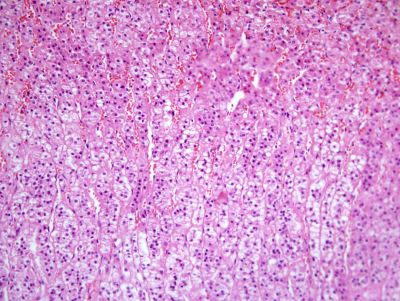

Adrenal gland - histology slide

This is a histology slide of the adrenal gland. 200X magnification.